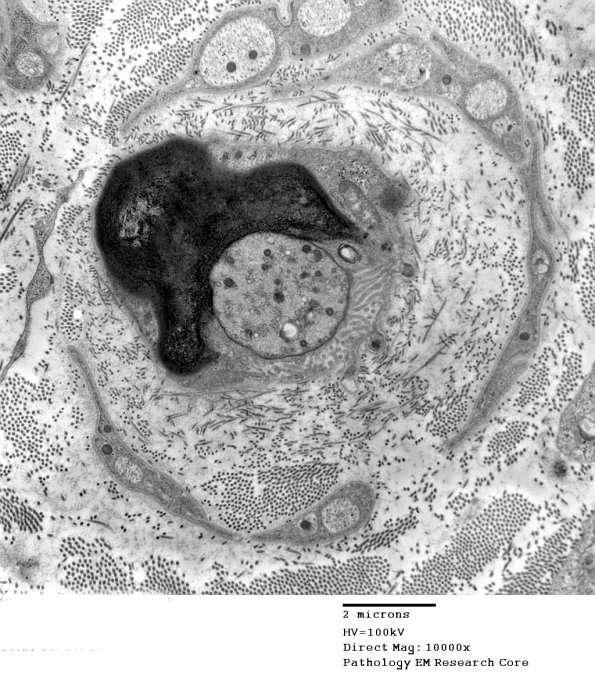

7A1,2 In some cases there is asymmetry of the myelin sheath and the microvilli may only occupy a portion of the axonal circumference. (electron micrographs)